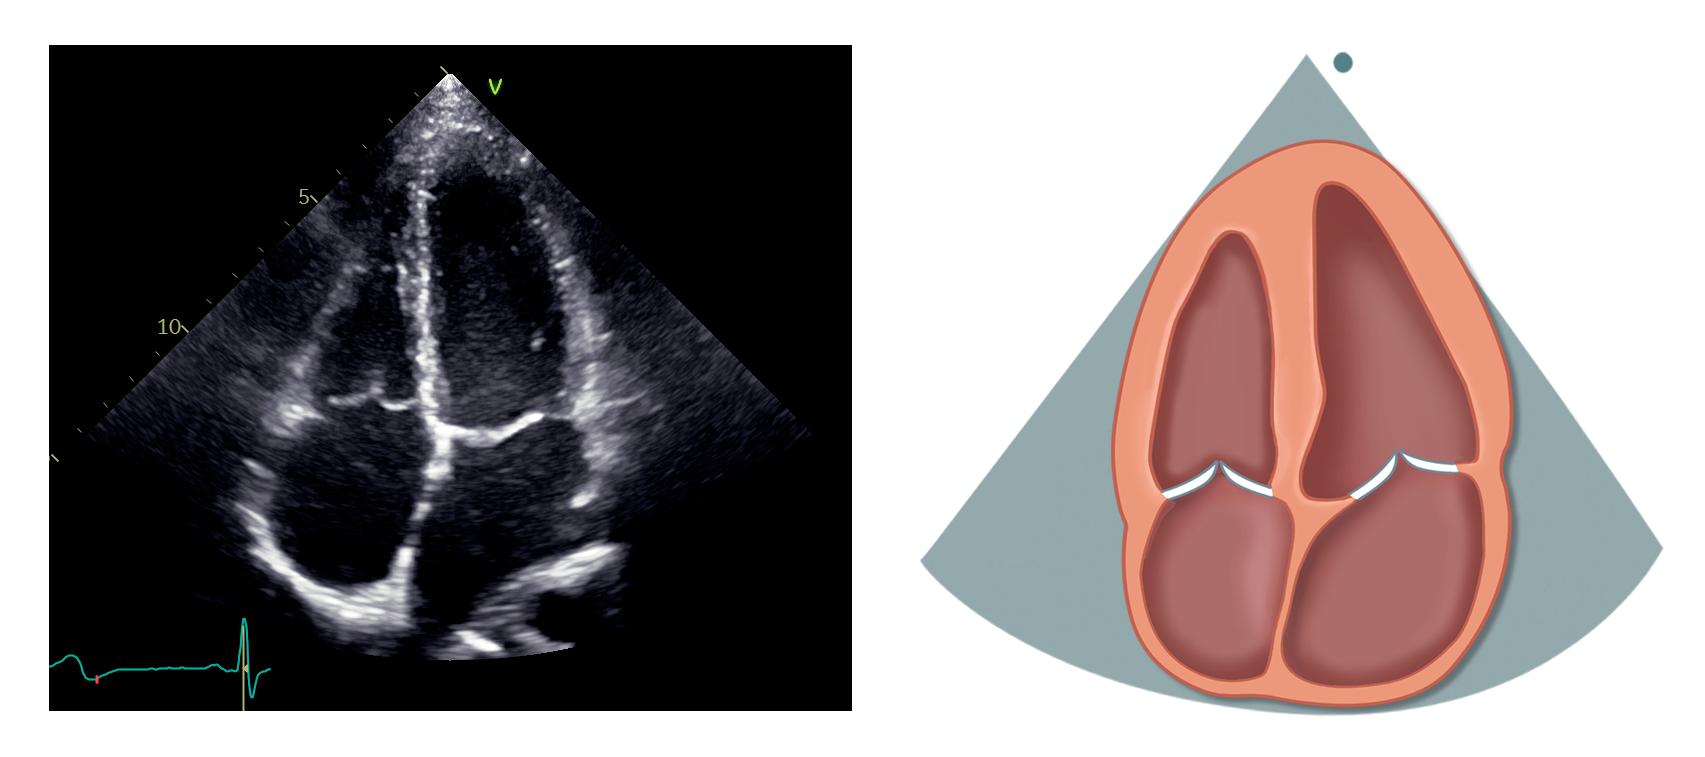

Apikal 4-kammerprojeksjon

Pasienten ligger fortsatt på siden mot venstre. Transduseren flyttes til femte interkostalrom omtrent i fremre aksillærlinje, over apex (palper gjerne etter ictus cordis). Markøren på transduseren skal peke omtrent mot klokken 3. Husk å unngå forkortning av venstre ventrikkel, det ses ved at apex har en avrundet

form og tykt myokard. Løsningen kan i så fall være å flytte transduseren ett interkostalrom lenger ned eller mer lateralt. Man vil også se at hjertet vil flytte seg ned når pasienten puster inn.

Venstre ventrikkel skal være formet som en geværkule, og ventrikkel- og atrieseptum skal være sentralt plassert og gå rett vertikalt i bildet. Ofte må plasseringen av transduseren eller pasientens leie justeres underveis for å få et best mulig bilde.

Apikal 4-kammerprojeksjon er svært nyttig og fremstiller alle fire hjertekamre, mitral- og trikuspidalklaff (figur 2.6).

Venstre ventrikkel med inferiore septum, apex og anterolateralveggen ligger øverst til høyre. Høyre ventrikkel ligger øverst til venstre. Atriene ligger nederst i bildet. Mitralklaffen er plassert mellom venstre atrium og ventrikkel med det fremre seilet til venstre og det bakre til høyre. Trikuspidalklaffen ligger mer apikalt enn mitralklaffen. Det septale seilet ses ved septum, mens det andre trikuspidalseilet i bildet er enten det fremre eller det bakre. Lungevenene ses munne ut i venstre atrium, eventuelt visualiseres de bedre med litt justering av transduserens plassering eller vinkling. Dersom vi er heldige kan tre av venene ses i standard apikal 4-kammerprojeksjon, mens den siste, som er den øvre høyre venen, kan ses med litt

26 K APITTEL 2

Høyre ventrikkel (HV) Høyre atrium (HA) Ventrikkelseptum (IVS) Venstre ventrikkel (VV) Trikuspidalklaffen (TK) Venstre ventrikkel (VV) HA HV IVS MK TK IAS VA VV Mitralklaffen (MK) Atrieseptum (IAS) Venstre atrium (VA) Figur 2.6: Apikal 4-kammerprojeksjon

mer anterior vinkling av transduseren i retning apikal 5-kammerprojeksjon.

Dersom transduseren vinkles posteriort (kaudal retning) kan sinus coronarius ses som et kar løpende langs gulvet av venstre atrium med utmunning i septale del av høyre atrium.

Tabell 2.5 lister opp sentrale målinger i apikal 4-kammerprojeksjon.

Tabell 2.5: Sentrale målinger i apikal 4-kammerprojeksjon

Målinger i apikal 4-kammerprojeksjon

Venstre ventrikkels volum og ejeksjonsfraksjon (EF) (Simpsons metode)

Venstre atriums volum (Simpsons metode, endesystolisk)

Høyre atriums volum (endesystolisk)

Pulset doppler ved tuppen av de åpne mitralseilene i diastolen

TAPSE (M-modusekkokardiografi)

Kontinuerlig doppler over trikuspidalklaffen

Pulset doppler i en lungevene (målevolumet plassert 10 mm fra innmunningen til venstre atrium)

Vevsdoppler i laterale og septale mitralannulus

Apikal 4-kammerprojeksjon – fokusert over høyre ventrikkel

Transduseren roteres litt mot klokken fra standard apikal 4-kammerprojeksjon, eventuelt må transduseren hos noen vinkles mer mot høyre ventrikkel eller flyttes lenger medialt og ett interkostalrom opp.

Poenget med denne projeksjonen er å få frem den reelle størrelsen av høyre ventrikkel og å vurdere den systoliske funksjonen. Trikuspidalklaffen kommer også bedre frem enn i standard apikal 4-kammerprojeksjon.

Tabell 2.6 lister opp sentrale målinger i apikal 4-kammerprojeksjon – fokusert over høyre ventrikkel.

Tabell 2.6: Sentrale målinger i apikal 4-kammerprojeksjon fokusert over høyre ventrikkel

Målinger i apikal 4-kammerprojeksjon – fokusert over høyre ventrikkel

Dimensjoner av høyre ventrikkel (endediastolisk)

Fraksjonell arealendring av høyre ventrikkel